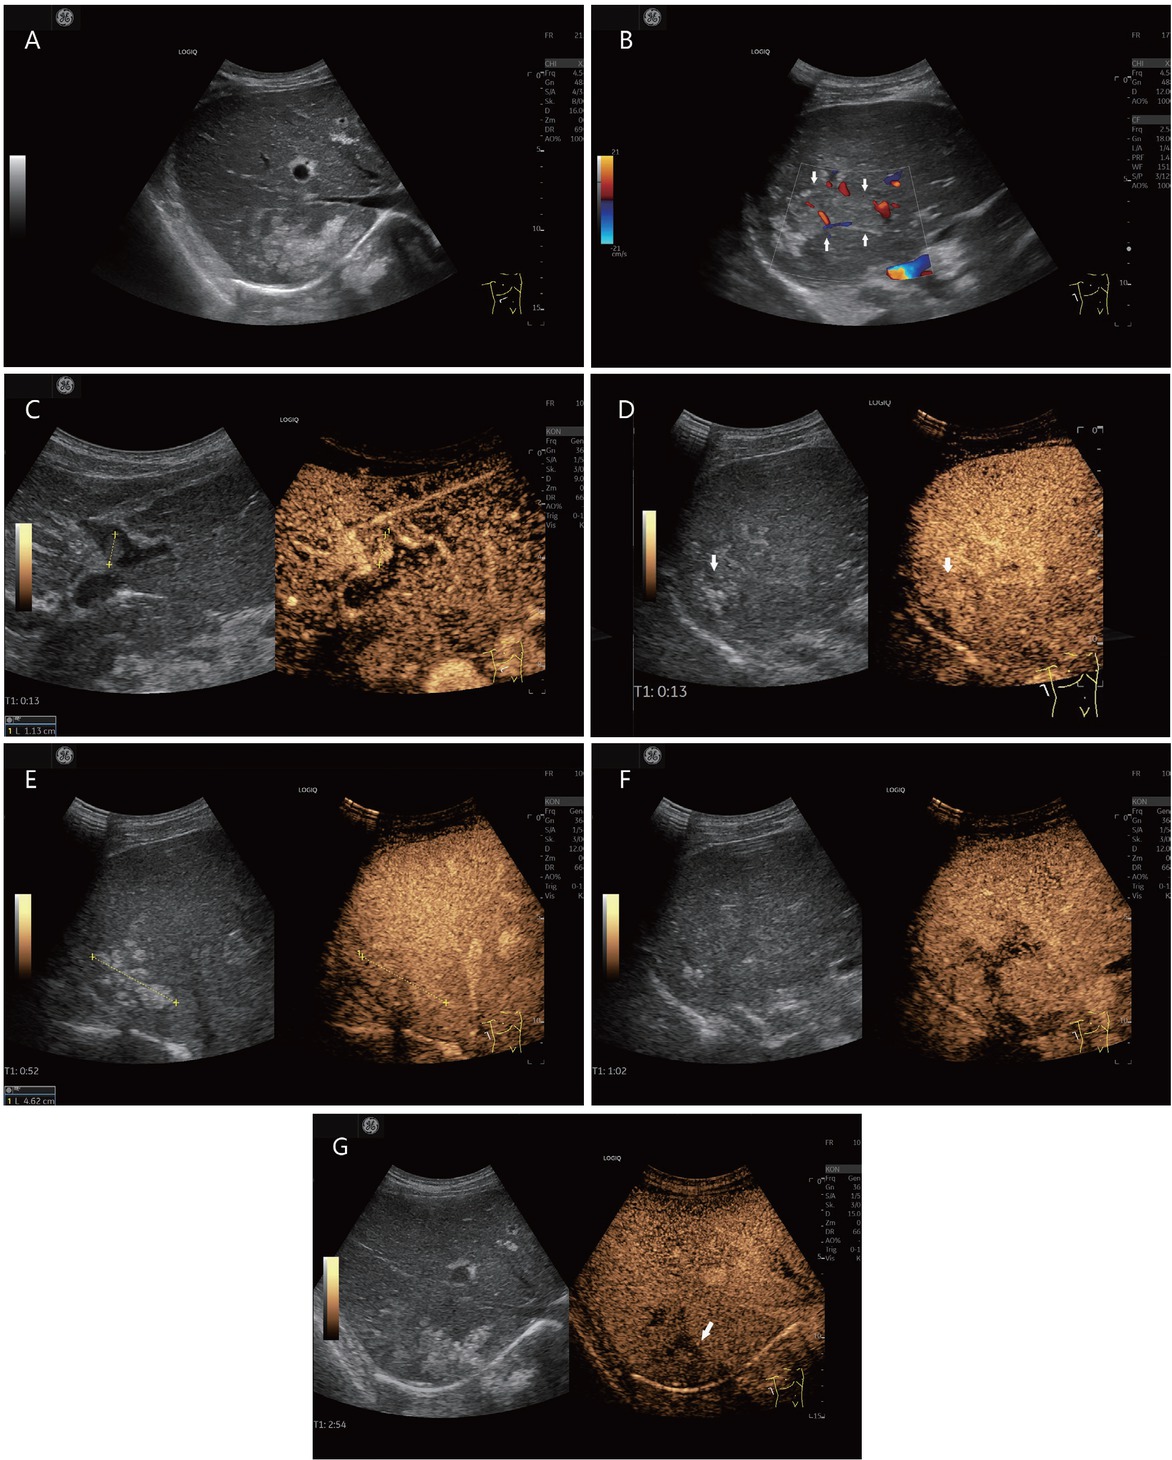

Metastases are classified as LR-M (Liver Imaging Reporting and Data System [LIRADS] malignant) in the CEUS-LIRADS algorithm.[12,14,40,91–93] In contrast to HCC, metastases often have a rim sign and usually an early washout in the portal venous phase.[9,19,72] In the study by Terzi et al.[8] with 848 patients with liver cirrhosis and 1006 nodules, 87% were malignant, but only 0.25% were metastases. These are classified as LM-R according to CEUS-LIRADS. The two metastases showed arterial phase rim enhancement or APHE and an early washout. The CEUS pattern LR-M showed few HCC, CCC, HCC/ CC, and lymphoma. The authors concluded that the LR-M class requires histologic confirmation (Figure 5).[8]

Liver metastases in a liver cirrhosis (histologically confirmed [in between markers and shown by arrows]). A 78-year-old male presented with hepatitis B and C and a history of continued alcohol abuse and operated sigmoid carcinoma. He currently had a peripheral lung lesion. AFP was normal. Computed tomography demonstrated hypodense liver lesions. Sonographically, irregularly circumscribed hyperechogenic liver lesions are seen subdiaphragmatically in the right liver lobe in B-mode (A). Adjacent to this, the right posterior branch of the ramus principalis is dilated and filled with thrombi (B). There is also a small thrombus in the pars umbilicalis, which is hyperenhanced in the arterial phase in CEUS, and thus corresponds to a tumor thrombus (C). On CEUS, the hyperechogenic lesions in the right hepatic lobe are isoechogenic, slightly inhomogeneously enhanced in the arterial (D) and portal venous (E) phases. The adjacent thrombosed portal venous branch is hypoenhanced (F). In the late phase, the liver lesions are hypoenhanced (G). CEUS was used to perform ultrasonography-guided puncture of the liver lesions and the thrombosed portal vein branch. Histologically, a metastasis of the sigmoid carcinoma was found. There was no evidence of hepatocellular carcinoma. CEUS: contrast-enhanced ultrasonography; AFP: alpha-fetoprotein.